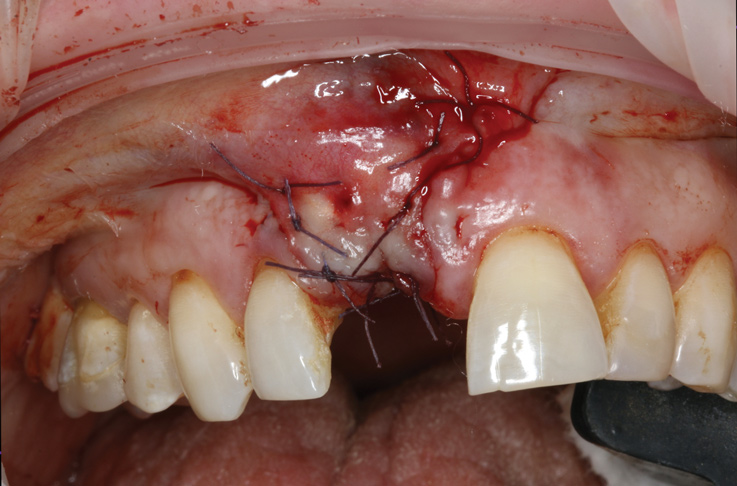

10. Tooth No. 8 with diagnosis of Grade III socket, requiring extraction followed by guided bone regeneration and a rotated pedicle flap to gain hard and soft tissue for future implant placement.

Figure 10

11. Tooth No. 8 with diagnosis of Grade III socket, requiring extraction followed by guided bone regeneration and a rotated pedicle flap to gain hard and soft tissue for future implant placement.

Figure 11

Based on the single extraction socket roadmap developed by El Chaar and colleagues, the socket of tooth No. 8 was diagnosed as Grade III and would require initial treatment that included the extraction of failing tooth No. 8 followed by simultaneous guided bone regeneration and soft-tissue augmentation by means of a rotated palatal pedicle flap (Figure 8 through Figure 11).27,28 The principles of and guidelines for both the ridge augmentation and rotated pedicle flap have been described in the literature and will not be focused on in this case report.27-30 The patient was temporized with a bonded Maryland bridge that was adjusted to avoid creating pressure on the tissue during healing (Figure 12).